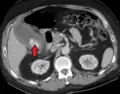

| Acute cholecystitis as seen on CT. Note the fat stranding around the enlarged gallbladder. | |